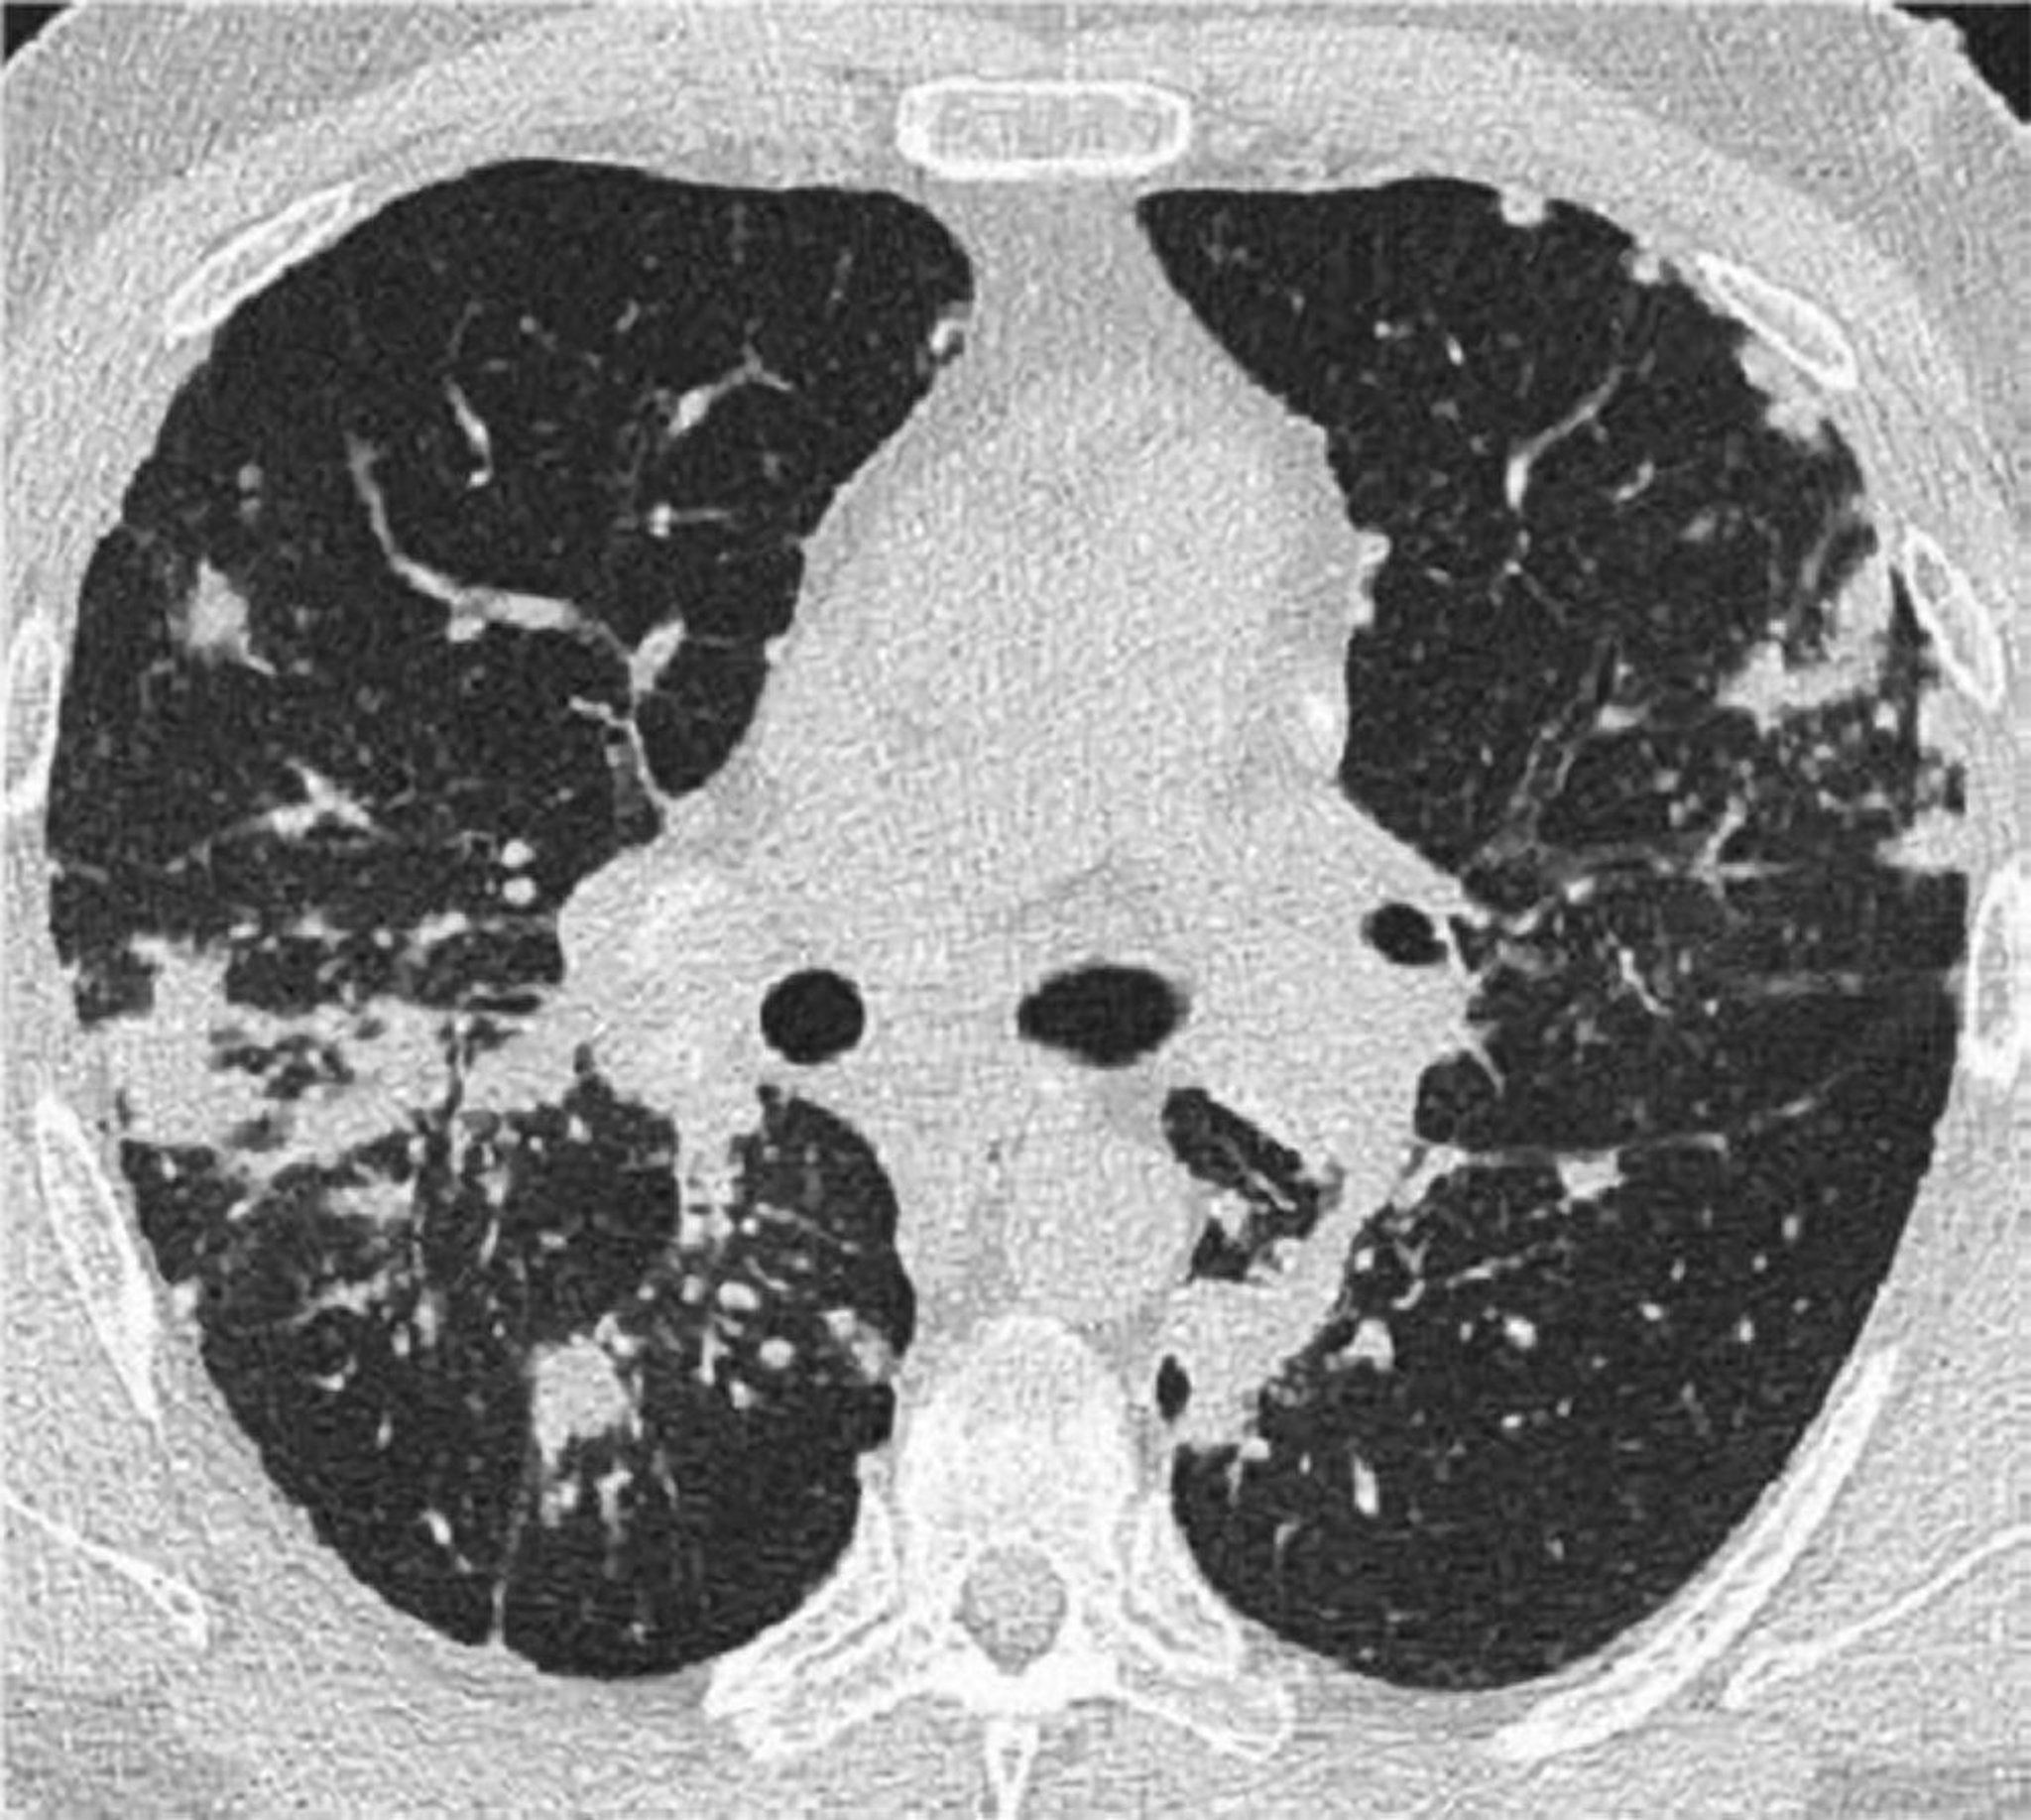

This high-resolution CT of the chest of a patient with pulmonary sarcoidosis shows thickening of the bronchovascular bundles and beading of the interlobular septa.

Image courtesy of Birendra P. Sah, MD, FCCP.